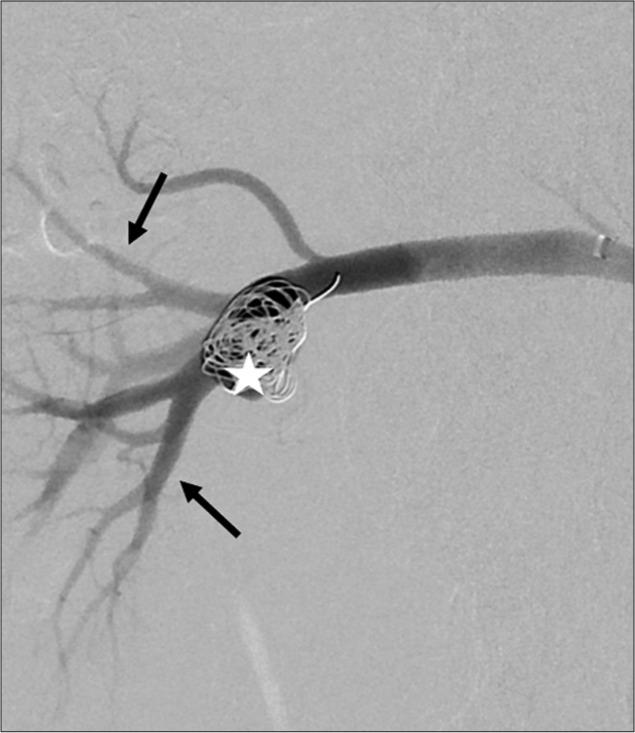

Advances in endovascular approaches have resulted in increasing utilization of minimally invasive techniques to treat visceral artery aneurysms including renal artery aneurysms (RAAs), with high rates of success. The basic endovascular approach to treating RAAs includes stent graft exclusion or coil embolization. Treatment of RAAs with wide necks or at the bifurcation of the main vessel is facilitated by scaffolding techniques, which have been previously described. These techniques have their limitations and cannot be used in all situations. We describe a scaffolding technique using the Comaneci device (Rapid Medical, Israel), a retrievable mesh device meant for intracranial treatment of wide neck or bifurcation aneurysms that we used to safely and successfully treat a 2 cm RAA.

血管内治疗方法的进展使得包括肾动脉动脉瘤(RAA)在内的内脏动脉瘤的微创技术使用率不断提高,成功率很高。治疗RAA的基本血管内方法包括支架移植物置入术或弹簧圈栓塞术。先前已描述过的支架技术有助于治疗颈部较宽或位于主血管分叉处的RAA。这些技术有其局限性,并非适用于所有情况。我们描述了一种使用科马内奇装置(以色列快速医疗公司)的支架技术,该装置是一种可回收的网状装置,用于颅内宽颈或分叉动脉瘤的治疗,我们用它安全、成功地治疗了一例2厘米的RAA。